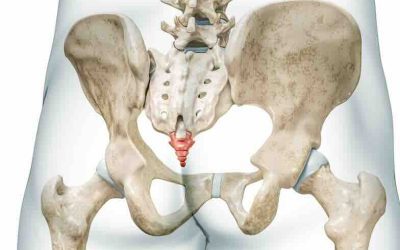

Coccigodinia: Qué es, síntomas y tratamiento

La coxigodinia o coccigodinia es el dolor del coxis, así es cómo se llama el último hueso de la columna, y fue descrita por primera vez en 1859 por Simpson...